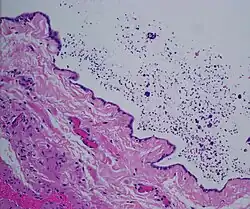

The primary care physician may diagnose and manage benign causes of scrotal masses such as hydrocele, varicocele and spermatocele. However, if a "must not miss" diagnosis related to testicular masses such as testicular torsion, epididymitis, acute orchitis, strangulated hernia and testicular cancer is suspected, the family physician must refer to a urologist.[19] Finding a painless, cystic mass at the head of the epididymis that is clearly separate from the testicle can indicate a spermatocele. Shining a light through the mass, a process known as transillumination, can also help differentiate between a fluid-filled cyst and a tumor, which would not allow as much light to pass.[20] If uncertainty exists, ultrasonography of the scrotum can confirm the presence of a spermatocele.[7] The location and history of any scrotal masses are crucial in determining whether or not the mass is benign or malignant.[21] Lab tests such as a complete blood count (CBC test) or urine test can also be conducted to check for any possible infection or signs of inflammation.[22]

Spermatoceles come in varying sizes and shapes. Some spermatoceles are very small and can only be detected through an ultrasound. More commonly seen are spermatoceles that are a pea-sized lump. They tend to form above or behind a testicle and have a shape and size that looks like a pea. Larger growths have been reported to look similar to a third testicle and can be very discomforting.[22] For those who are affected with large spermatoceles, some have reported feeling pain, heaviness, and fullness in the affected testicle.[20]